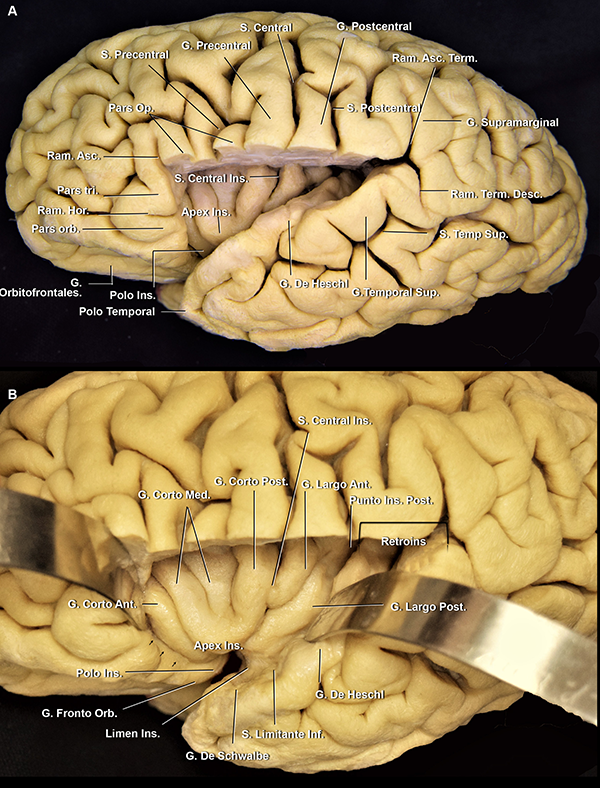

La FS se divide en una sección lateral y una basal. El punto divisor arbitrario entre ellas es el limen insular, definido como un área anatómica arqueada que se extiende desde el punto donde el giro largo insular posterior se fusiona con el plano polar del lóbulo temporal, hasta los giros fronto-orbitarios. El limen insular se relaciona superficialmente con el vértice inferior de la pars triangularis del giro frontal inferior. El mismo oficia como eje para el cambio de dirección de la arteria cerebral media (ACM) (Figura 1).

La FS presenta tres niveles de profundidad: la parte superficial, intermedia y profunda (Figura 2). La parte superficial se compone de un tronco (en la superficie basal) y tres ramos (en la superficie lateral). La parte intermedia y profunda, denominadas en conjunto como la cisterna silviana, están compuestas por el compartimiento operculoinsular anterior (en la superficie basal) y lateral (en la superficie lateral) (Tabla 1).

El tronco silviano se extiende hasta la punta inferior de la pars triangularis. En dicho vértice, se originan los tres ramos. Este punto es conocido como punto silviano anterior (Figura 3).

Los ramos de la FS son: 1) el ramo horizontal, 2) el ramo ascendente y 3) el ramo posterior, que cursa entre la parte posterior del opérculo frontoparietal y el temporal, y usualmente finaliza como una bifurcación en el giro supramarginal: el ramo ascendente terminal y el ramo descendente terminal. Este último, suele ser más corto que el anterior y es inconstante. El punto silviano posterior está ubicado en el extremo distal del ramo posterior, en el punto donde los ramos terminales se originan (Figura 3). Se describen dos ramos adicionales que se originan en el ramo posterior: el surco subcentral anterior y posterior (Figura 4A). Estos dos surcos se localizan anterior y posterior al surco central, respectivamente. Por detrás del punto silviano anterior, se encuentra el punto rolándico inferior (Figura 3). El punto rolándico inferior es definido como el punto de encuentro entre el surco central y la FS. Sin embargo, en el 70% de los casos de nuestra serie, el surco rolándico no se intersectó directamente con la FS en la superficie lateral del cerebro. Consecuentemente, el punto rolándico inferior también se refiere al punto de intersección de la proyección del surco central con la FS.

La parte profunda de la FS tiene una organización más compleja. La parte cisternal en la superficie basal del cerebro se extiende desde la estría olfatoria lateral hasta el limen insular (Figura 1A). Está compuesta por 1) el compartimiento opercular anterior, en un nivel intermedio de profundidad, y 2) la hendidura insular anterior y el compartimiento esfenoidal, en el nivel más profundo (Figura 1).

El compartimiento opercular anterior se define como el espacio entre los giros orbitarios posterior y lateral y el plano polar del lóbulo temporal (Figura 5A y 6B). Por otro lado, la hendidura insular anterior se localiza entre la ínsula y los giros orbitarios lateral y posterior (Figura 1C,6B,7A).

Distalmente al limen insular, en la profundidad de los ramos superficiales, presentando una orientación diagonal, se localiza la parte cisternal lateral de la FS. Este segmento es también conocido como compartimiento operculoinsular lateral. Este compartimiento se encuentra compuesto por tres espacios estrechos: 1) el compartimiento opercular lateral, entre el opérculo frontoparietal y temporal, en un nivel intermedio, 2) la hendidura insular lateral y 3) la región retroinsular (Figura 6). Los últimos dos espacios se encuentran en el nivel más profundo de la cisterna silviana. La hendidura insular lateral se localiza entre la ínsula y los opérculos, extendiéndose desde el limen insular hasta el punto en el que los surcos limitantes insulares superior e inferior se conectan, punto conocido como punto insular posterior. Dicha hendidura tiene un bolsillo superior e inferior. La región retroinsular se extiende desde el punto insular posterior hasta el extremo distal de la FS. Esta región se relaciona superficialmente con el giro supramarginal, superiormente, y los giros temporales transversos, inferiormente (Figura 6B).

Figura 3: Vista lateral de un hemisferio cerebral derecho. Estrella azul: punto silviano anterior. El limen insular, el genu de la ACM y, frecuentemente, la bifurcación de la ACM se localiza medial e inmediatamente anterior a este punto. Estrella naranja: punto rolándico inferior. Estrella roja: punto silviano posterior. La ínsula se proyecta lateralmente desde el ramo horizontal a la parte más anterior del giro supramarginal; y desde la parte más superior de la pars triangularis y el ramo ascendente hasta el surco temporal superior. Línea punteada verde, azul y roja: proyección de los surcos semicirculares insulares anterior, superior e inferior, respectivamente. S: surco; G: giro; Ram: ramo; Sup: superior; Med: medio; Asc: ascendente; Desc: descendente; Term: terminal; Orb: orbitalis, Tri: triangularis; Op: opercularis; Hor: horizontal.

Figura 4: A. Vista latero inferior de un opérculo frontoparietal derecho. El opérculo temporal, la parte lateral del giro orbitario posterior y la parte posterior del giro orbitario lateral fueron removidas. Cuando el surco central no alcanza a la FS, el giro subcentral es visible en la cara lateral cerebral. En cambio, cuando sí lo hace, como en este caso, este giro se localiza en la profundidad de la fisura. Se observa cómo el ramo horizontal se continúa medialmente con el surco limitante anterior. El ápex insular se localiza superior y posteriormente al polo insular. B. Vista lateral del mismo espécimen. C. Vista de la superficie lateral de la ínsula de otro espécimen. Estrella azul: punto insular anterior. Estrella verde: punto insular posterior. S: surco; G: giro; Ant: anterior; Post: posterior; Op: opercularis; Ram: ramo; Hor: horizontal; Orb: orbitario; Ins: insular

Figura 5: A. Vista lateral de un hemisferio cerebral izquierdo. B. RMN, secuencia T1, corte sagital. La pars triangularis tiene forma de “V” (líneas rojas). Luego, encontramos 3 giro con forma de “U” (flechas azules), de anterior a posterior: 1) pars opercularis; 2) giro subcentral; y 3) la conexión entre los giros postcentral y supramarginal. Finalmente, la flecha verde marca la conexión con forma de “C” entre los giros supramarginal y temporal superior. Se observa al giro de Heschl enfrentado al postcentral. Ambos se encuentran en el mismo plano coronal que el CAE. Asterisco: proyección medial del CAE. S: surco; G: giro; Sup: superior; inf: inferior.

Figura 6: A. vista lateral de un hemisferio cerebral izquierdo. Se removió el opérculo frontoparietal, preservando la pars orbitalis y triangularis. La punta de la pars triangularis se ubica superficialmente al ápex insular e inmediatamente posterior al polo y limen insular. B. Mismo espécimen. La superficie insular anterior enfrenta a los giros frontoorbitarios y el espacio estrecho entre estas estructuras es la hendidura insular anterior (flechas negras). La región retroinsular se extiende desde el extremo posterior de la ínsula al extremo posterior de la FS. S: surco; G: giro; Ins: insular; Sup: superior; Ram: ramo; Term: terminal; Asc: ascendente; Desc: descendente; Op: opercularis; Orb: orbitalis; Tri: triangularis; Hor: horizontal

Figura 7:A. vista lateral del lóbulo insular izquierdo del mismo espécimen que en la figura 1D y 9D. La superficie lateral de la ínsula está totalmente cubierta por M2 y sus ramas. El limen insular (círculo sombreado azul) limita la parte basal de la lateral de la FS y el segmento M1 de M2. Las arterias corticales tempranas no tienen un segmento insular dado que nacen del segmento M1 y pasan directamente al M3. B. Vista superior del mismo espécimen. El opérculo frontoparietal fue removido. C. Vista inferior de la ínsula del mismo espécimen. Los giros cortos tienen una dirección hacia el ápex insular. Debajo del ápex, la proyección inferior de los giros cortos se dirige hacia el polo insular. Los giros posteriores largos empiezan en el plano polar como un giro único que luego se divide en dos. S: surco; G: giro; Ant: anterior; post: posterior; Ins: insular; Acc: accesorio; Tran: transverso; Inf: inferior; Sup: superior; Orb: orbital; Hend: hendidura; Tempr: temprana.

Techo: opérculo frontoparietal

El techo de la fisura silviana está conformado por los lóbulos frontal y parietal. La palabra operculum proviene del latín y significa “cortina”:21 los lóbulos frontal, parietal y temporal cubren armónicamente a la cisterna silviana e ínsula (Figura 5A).

El giro frontal inferior se divide por los ramos superficiales de la FS, de anterior a posterior, en la pars orbitalis, la triangularis y la opercularis (Figura 3 y 5A).

La pars orbitalis se continua basalmente con los giros orbitarios lateral y posterior. Es el área más prominente del giro frontal inferior (Figura 5A y 9A)22 y se relaciona superficialmente con el keyhole (agujero de trépano llave) del abordaje pterional.

La pars triangularis, que posee una forma de “V”,22,23 suele albergar un ramo originado del surco frontal inferior y cubre al ápex insular. Por otro lado, la pars opercularis, que tiene forma de “U”,22 alberga un ramo originado del surco precentral, o en su defecto, al extremo inferior del surco precentral (Figura 3 y 5). La pars opercularis, se recuesta superficialmente sobre el giro corto posterior de la ínsula (Figura 4A). Más aún, la rodilla de la cápsula interna y el foramen de Monro se ubican en la profundidad de dicho giro corto (Figura 12B). Finalmente, el área de Broca del lenguaje, se compone de la pars triangularis y opercularis del hemisferio dominante.22

El lóbulo central se localiza posterior a la pars opercularis y se compone de los giros pre y postcentral.18,22 El puente neural que conecta dichos giros en el extremo inferior del surco central es el giro subcentral, también denominado pli de passage frontoparietal inferior de Broca u opérculo rolándico (Figura 4A y 5A).22,23 El giro precentral se recuesta superficialmente sobre el tercio medio de la corteza insular y el cuerpo de los ventrículos laterales. El surco central corre en una dirección paralela al surco central de la ínsula. Está reportado en la literatura que hasta en el 84% de los casos, el surco no se extiende hasta contactar la FS, en consonancia con nuestros hallazgos.12,18 El giro postcentral se ubica superficial al tercio posterior de la ínsula (Figura 4A y B).

La parte más posterior del techo de la fisura silviana la conforma el giro supramarginal, que alberga al ramo terminal ascendente de la fisura silviana. El opérculo supramarginal envuelve al punto silviano posterior, conectando a los giros supramarginal con el temporal superior (Figura 3 y 5). En la profundidad del margen más anterior del giro supramarginal es encontrado el punto insular posterior, que marca a su vez el extremo posterior del lóbulo insular (Figura 6). Asimismo, el extremo posteromedial del giro de Heschl se localiza justo posterior al punto insular posterior (Figura 12B).

Piso: opérculo temporal

La parte opercular del giro temporal superior está dividida en dos: anteriormente, el plano polar o planum polare, y posteriormente, el plano temporal o planum temporale. La estructura neural que marca esta división es el giro transverso anterior o, simplemente, giro de Heschl. Este es el giro más voluminoso del opérculo temporal, tiene una orientación diagonal y su extremo posteromedial apunto hacia el brazo posterior de la cápsula interna, el núcleo pulvinar del tálamo y el atrio (Figura 12A, B, D).15,22

El plano polar es un área integrada por giros cortos oblicuos menores: los giros de Schwalbe (Figura 6B).25 Por un lado, tiene una orientación lateromedial en el eje axial, escondiendo su punta anterior debajo del giro orbitario posterior (Figura 6).15 Por otro lado, tiene una orientación oblicua inferior en el eje coronal, que contribuye al agrandamiento del espacio subaracnoideo en el punto silviano anterior.22,23

El plano temporal está compuesto por dos o tres giros transversos. Es un área de forma triangular cuyo ápex apunta hacia el atrio ventricular. El giro de Heschl y la parte posterior del giro temporal superior constituyen el área auditiva primaria (Figura 6A, 10A y B).22 En su extremo anterolateral, el giro de Heschl se encuentra en el mismo plano coronal que el giro postcentral. Además, se evidenció que el giro de Heschl a su vez se encuentra en el mismo plano que el conducto auditivo externo (CAE) (Figura 5). En el plano coronal, tiene una orientación horizontal, haciendo que la disección de la fisura en esta área sea más dificultosa.

Pared medial: lóbulo insular

La ínsula tiene forma piramidal, con un ápex anteroinferior (Figura 4C y 6B). Tiene una superficie anterior y otra lateral. Está rodeada por el surco limitante semicircular de la ínsula, que está dividido en tres partes: anterior, superior e inferior (Figura 12A y C).

La superficie anterior de la ínsula se relaciona con los giros orbitarios posterior y lateral, que la recubren.15 El espacio que existe entre estas dos estructuras neurales es la llamada hendidura insular anterior, que es parte del compartimiento operculoinsular anterior (Figura 1C y 7A). Tiene una parte superior compuesta por dos giros verticales paralelos: el giro accesorio y el giro corto insular anterior; y una parte inferior, compuesta por el giro transverso de Eberstaller (Figura 4A). El giro accesorio se fusiona con este giro transverso que a su vez se continúa en la superficie basal del cerebro, ininterrumpidamente, con los giros orbitarios posterior y medial.

El polo insular es definido como la región más anteroinferior de la ínsula. Está localizado lateral al limen insular (Figura 4A, 4C, 7C). El límite medial de la superficie anterior es el surco limitante anterior de la ínsula (Figura 4A y B).

La superficie lateral de la ínsula está dividida por el surco central de la ínsula en una parte anterior y otra posterior. La parte anterior representa dos tercios de la superficie lateral de la ínsula (Figura 4C y 6B). El surco central de la ínsula está orientado en paralelo al surco central y es el área insular más densamente vascularizada (Figura 7A).27 El extremo inferior del surco central insular apunta al limen. Los giros cortos anterior, medio y posterior se encuentran en la parte anterior de la ínsula, aunque se han descripto tanto como cinco giros cortos (Figura 6B).6,26

El ápex insular es el área más lateral, superficial y prominente de la ínsula, y es el punto de encuentro de los giros cortos insulares (Figura 7A, 12A, 12C). Está localizado superolateralmente al polo insular. La continuación basal de los giros cortos insulares está dirigida hacia la parte superior del polo insular (Figura 7C).

Posterior al surco central insular, los giros largos anterior y posterior son encontrados. Los giros largos se originan como un giro único cerca del limen insular, que luego se divide por un surco largo posterior (Figura 12B).

La parte anterior de la superficie lateral de la ínsula está cubierta por la pars triangularis, opercularis y el giro precentral, superiormente; y por el plano polar, inferiormente. La parte posterior, está cubierta por el giro postcentral y el giro de Heschl (Figura 5A y 6A). También, en la superficie lateral del cerebro, el surco limitante anterior se continúa con el ramo horizontal de la FS; el surco limitante superior se proyecta como una línea horizontal que pasa sobre la base de la pars triangularis y el extremo superior del ramo ascendente; y, finalmente, el surco limitante inferior se proyecta sobre el surco temporal superior (Figura 6). Entonces, la proyección superficial de la ínsula en la superficie lateral del cerebro va desde el margen anterior de la pars triangularis, anteriormente, al margen anterior del giro supramarginal, posteriormente (Figura 3).15